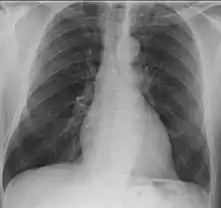

- Lungs: abnormal chest X-ray with:

- nodules,

- infiltrates or

- cavities

- Lungs: pulmonary nodules (referred to as "coin lesions"), infiltrates (often interpreted as pneumonia), cavitary lesions, bleeding in the lungs causing a person to cough up blood, and rarely bronchial stenosis.